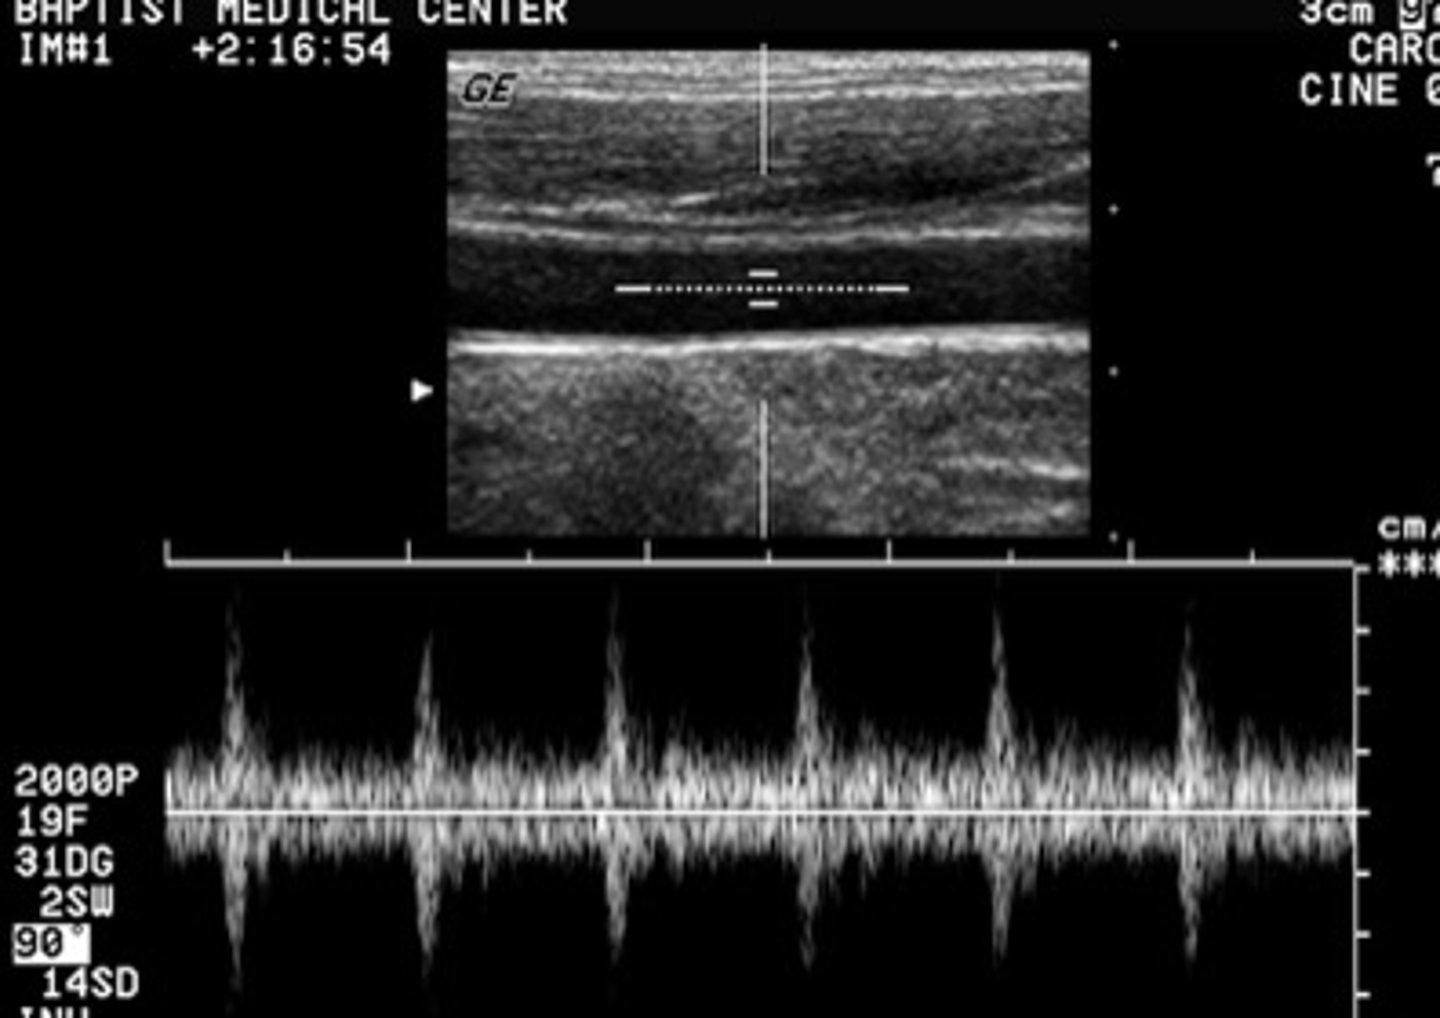

Which term below most correctly describes this Doppler waveform?

spectral mirroring

<p>spectral mirroring</p>